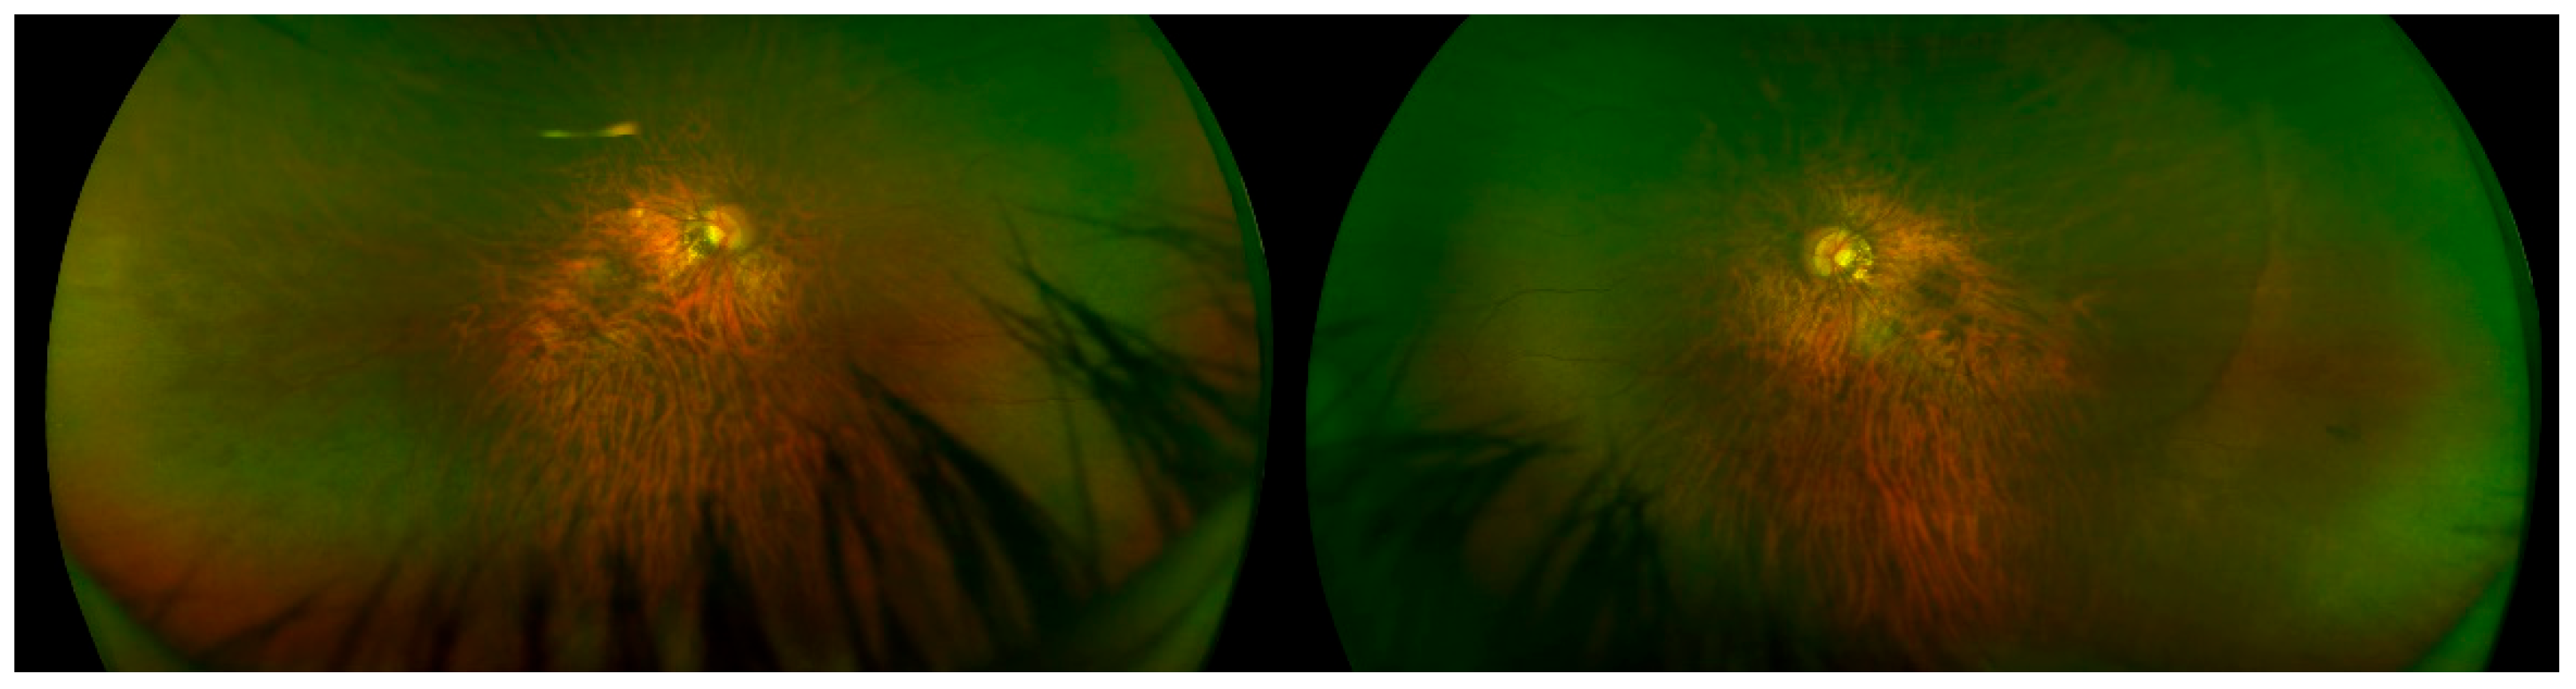

| OFT-00559 | M | 0.4 | 0.3 | NA | NA | Diffuse increase in vascular ramification, Avascular peripheral retina | Avascular peripheral retina | −7 | −1.25 | −7.625 | −7.5 | −1.75 | −8.375 |

| OFT-00559 | EoHM | NYSTAGMUS | NDP | NM_000266.4 | c.313_314delGCinsTT: p.Ala105Leu | PM1, PM2, PM5, PS1, PP2, PP3 | P | Deletion/Insertion | Hemi | S | No | Unknown | Novel ** |